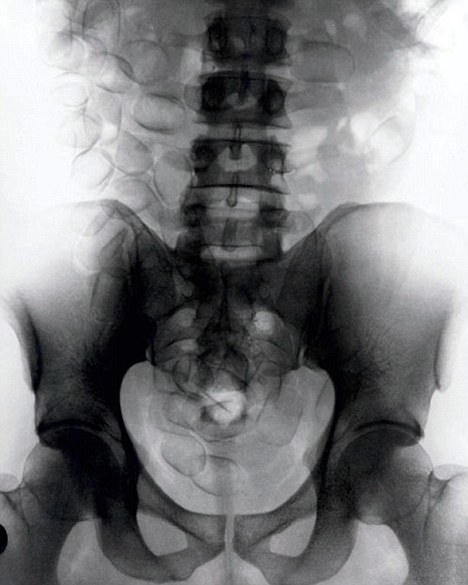

X光顯示:男子吞下67包可卡因

現年30歲的菲達利斯(Fidelis Ozouli)冒著生命危險將重達1公斤的毒品吞下,被抓后卻辯稱不知道吞下的是毒品。當時,曼徹斯特機場的海關人員看到毒販菲達利斯臃腫的肚腩,顯得很不自然,于是開始懷疑。檢查人員用X射線機照他的胃部時,發現了大量可卡因。目前他已被送往附近醫院,以確保排出所有的毒品。